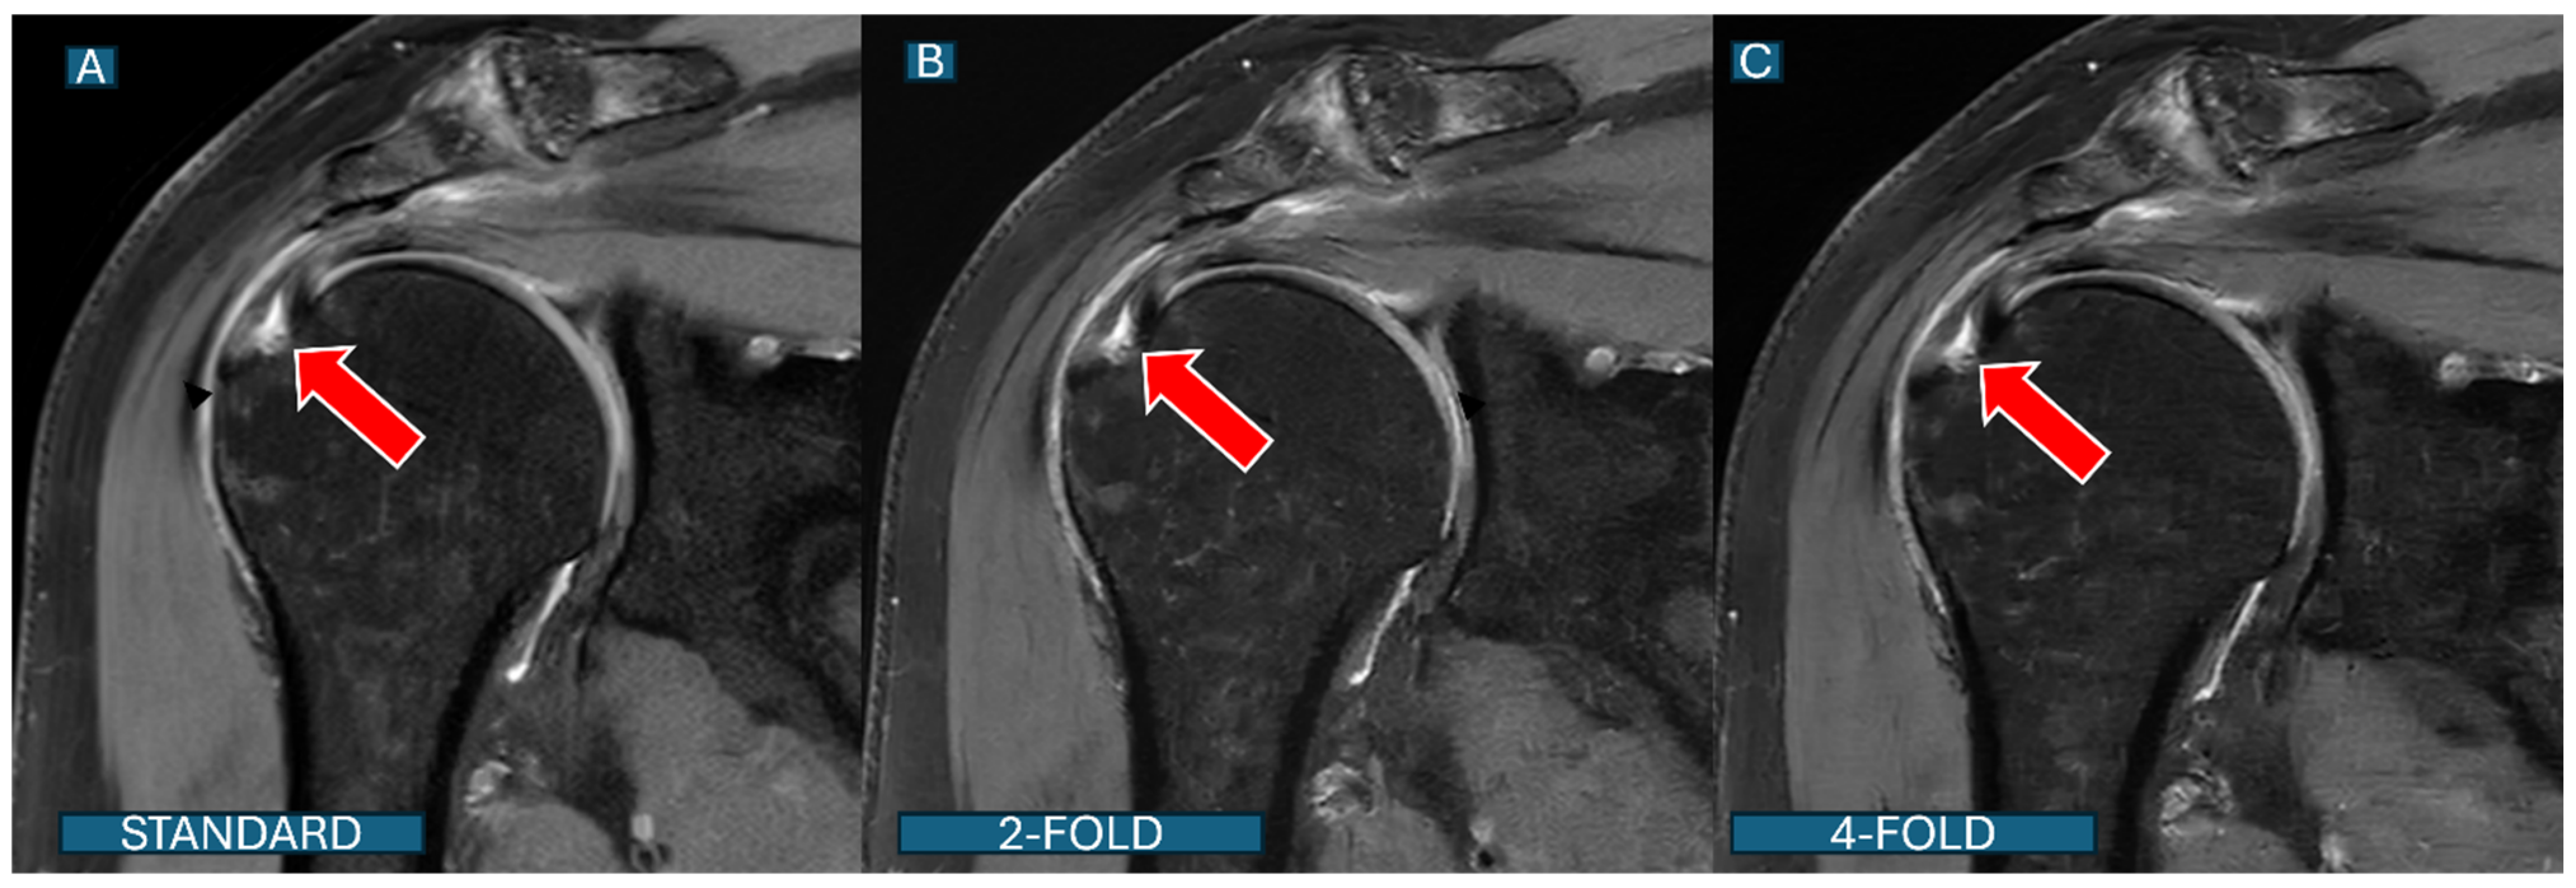

An ROC curve analysis demonstrated excellent results for both protocols. The DL2 protocol achieved an AUC of 0.94 (95% CI: 0.91–0.97), while the DL4 protocol showed an AUC of 0.90 (95% CI: 0.87–0.93). A statistical comparison using DeLong’s test revealed no significant difference between the protocols (p = 0.32), suggesting that both acceleration levels maintain clinically acceptable diagnostic accuracy (Figure 2). An overall diagnostic accuracy comparison between the DL2 and DL4 protocols stratified by reader experience, aggregating all pathologies (bone marrow edema, rotator cuff tears, and labral tears), is well documented in Figure 3. Some illustrative clinical cases are shown in Figure 4, Figure 5, Figure 6 and Figure 7, with Figure 7 specifically illustrating a case where pathology detection was compromised in the DL4 protocol compared to the standard and DL2 protocols.

Second, the DL reconstruction process at higher acceleration factors may introduce subtle blurring or smoothing effects that can obscure fine structural details that are critical for detecting partial tears. This phenomenon was particularly evident in partial-thickness supraspinatus tears near the footprint, as illustrated in Figure 7. The subtle hyperintensity representing a small articular-sided tear is clearly visible on standard images, slightly less conspicuous on DL2 images, and often not discernible on DL4 images.

Figure 7. Partial-thickness rotator cuff tear: detection differences across protocols. Coronal fat-saturated PD images of a 52-year-old patient show an articular-sided partial tear of the supraspinatus tendon (red arrows). (A): The standard protocol clearly shows the subtle hyperintensity representing a partial tear near the footprint; (B): under the DL2 protocol, the tear remains visible but with slightly reduced conspicuity; (C): under the DL4 protocol, the subtle tear is substantially less conspicuous and could be missed in clinical interpretation. This case illustrates the potential diagnostic limitations of higher acceleration factors for subtle pathologies.